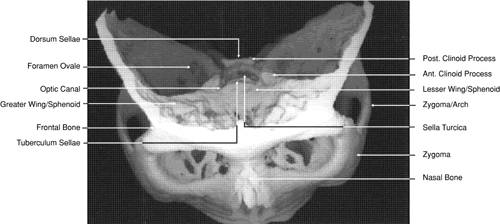

Fig. 29. A. Axial computed tomography soft tissue image at the level of the base of skull. B. Axial computed tomography bone window image at the level of the base of skull.

Fig. 30. A. Axial T1-weighted image at the level of floor of orbit and trigeminal nerve. B. Axial T1-weighted image at the level of oculomotor nerve.

Fig. 31. Axial T1-weighted image through the cerebral peduncle at the level of oculomotor nerve.

Fig. 32. A. Axial computed tomography soft tissue image at the level of suprasellar cistern. B. Axial computed tomography soft tissue image at the level of thalamus. C. Axial T1-weighted image at the level of thalamus.

Fig. 33. Sagittal T1-weighted image of the brain through the interhemispheric fissure.

The orbital floor is similar in shape to the triangular orbital roof and is composed of the maxillary, zygomatic, and palatine bones. Medially, the bony lacrimal canal containing the nasolacrimal duct lies just posterior to the inferior orbital rim (see Fig. 22). At this point the canal is formed by the maxillary and lacrimal bones. Just lateral to the bony canal is the origin of the inferior oblique muscle. Laterally, the floor is separated from the lateral orbital wall by the inferior orbital fissure, which begins lateral and inferior to the optic foremen and near the inferior aspect of the superior orbital fissure. It is approximately 20 mm long, ending 20 mm posterior to the lateral portion of the inferior orbital margin (see Fig. 14). The boundaries of the fissure are the maxillary and palatine bones medially, the greater wing of the sphenoid bone posteriorly, and the zygomatic bone laterally and anteriorly. Inferior to the orbital floor over most of its area is the maxillary sinus (see Figs. 5, 19, and 26). The bone of the floor is 0.5 to 1.0 mm thick, being thinnest at the inferior orbital groove and canal. The fragility of this bone is the reason it is commonly fractured during orbital trauma and the reason for orbital extension of sinus tumors. The ethmoid air cells are occasionally found within the orbital floor medially, and posteriorly there may be a sinus within the orbital portion of the palatine bone.48 The medial rectus muscle runs along the middle aspect of the floor until it inserts into the globe. It is in contact with the floor posteriorly, but anteriorly it is superior to the inferior oblique muscle (see Fig. 19).

The inferior orbital fissure is associated with several important soft tissue and bony structures. The maxillary division of the trigeminal nerve enters the fissure through the foremen rotundum and pterygopalatine fossa, dividing into the infraorbital and zygomatic nerves (see Figs. 20 and 21). This latter nerve separates into the zygomaticofacial and zygomaticotemporal nerves entering the zygomatic bone of the lateral orbital wall through small canals before exiting onto the face. The pterygopalatine fossa is bounded anteriorly by the pterygoid process of the sphenoid bone, the greater wing of the sphenoid, the maxilla, and the palatine bone (see Figs. 21 and 29). In addition to the maxillary division of the trigeminal nerve, it contains the pterygopalatine ganglion and its sensory, parasympathetic, and sympathetic branches and a portion of the maxillary artery. It communicates with the orbit by way of the inferior orbital fissure, the nasal cavity through the sphenopalatine foremen, and with the infratemporal fossa by way of the pterygomaxillary fissure. In addition to the foremen rotundum, sphenopalatine foremen, and pterygomaxillary fissure, the pterygoid and pharyngeal canals also enter into the fossa (see Fig. 29). After leaving the pterygopalatine fossa, the infraorbital nerve travels in the inferior orbital fissure a short distance before turning directly anteriorly into the infraorbital groove and canal within the maxillary bone. Finally it exits from the anterior surface of the bone 4 to 6 mm inferior to the midportion of the inferior orbital rim (see Fig. 19). The infraorbital artery, a terminal branch of the internal maxillary artery, accompanies the nerve along most of its course. Other branches of the maxillary division of the trigeminal nerve include branches to the pterygopalatine ganglion and the posterior, medial, and anterior superior alveolar nerves, which supply sensation to the upper teeth and gums.

The superior orbital fissure separates the orbital roof from the lateral orbital wall and the lesser and greater wings of the sphenoid bone (see Figs. 13 and 14). The common tendinous ring (annulus of Zinn) of the extraocular muscles and the spine for the insertion of the lateral rectus muscle separates the fissure into a thin superolateral portion and a wide inferomedial portion (see Fig. 21). The fissure is approximately 22 mm long, and its superior end is 30 to 40 mm from the frontozygomatic suture.48 Directly posterior to the fissure are the middle cranial fossa and temporal lobe. Passing through the superior portion of the fissure above the tendinous ring are the lacrimal (cranial nerve V), frontal (cranial nerve V), and trochlear (cranial nerve IV) nerves, the superior ophthalmic vein, and the recurrent lacrimal artery. Passing within the ring are the superior division of the oculomotor nerve (cranial nerve III) and the abducens nerve (cranial nerve VI) laterally, the nasociliary nerve (cranial nerve V) and the inferior division of the oculomotor nerve medially, and the sympathetic root of the ciliary ganglion and the inferior ophthalmic vein, which on occasion may pass below the ring. The tendinous insertions of the lateral and inferior rectus muscles form the superior, lateral, and inferior portions of the ring in the area of the superior orbital fissure. There is no muscle tendon medial to the fissure. The medial border of the fissure is formed by a strut of bone from the lesser wing of the sphenoid bone, which separates it from the optic canal.